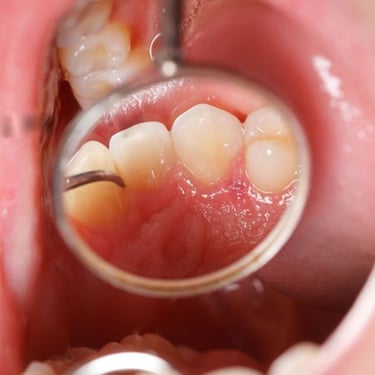

La periodoncia se encarga del diagnóstico y tratamiento de enfermedades que afectan las encías y el soporte dental.

Un tratamiento oportuno ayuda a evitar la pérdida dental y mantener una sonrisa sana.